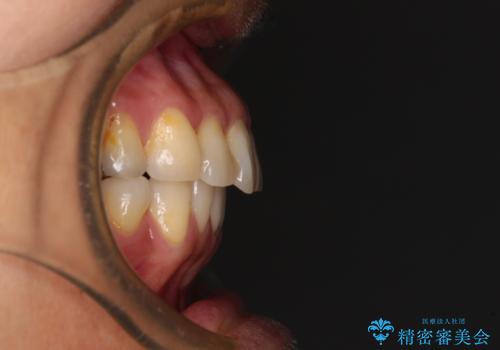

- 高校生の時に行った矯正治療の後戻りと、通院してもなかなか改善しない奥歯の痛みを気にして来院された患者様です。

左下奥歯は、前医より難治性なので抜歯も考えるよう言われたそうですが、一度もラバーダムを用いた根管治療はされていないとのことでした。

まずは左下奥歯の根管治療を行い、痛みが引いたことを確認してから矯正治療を開始しました。

後戻りは軽微であったため、インビザライン・ライトにて歯列を整えました。